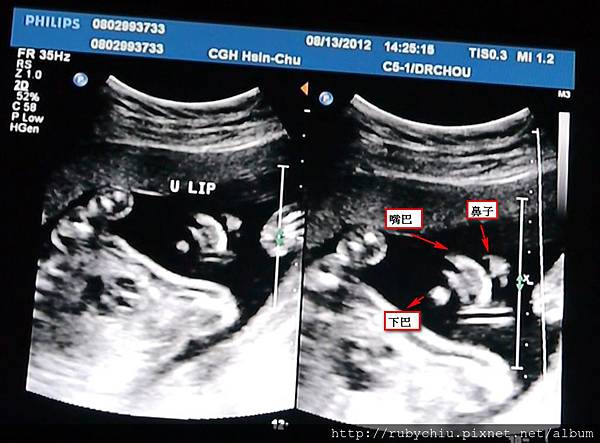

首圖是紀念品可愛的側臉,右邊則是由上往下拍的樣子~ 有眼睛跟鼻樑骨!

由下往上拍,拍到了她的鼻子啦!還有鼻孔!跟嘴巴~

爸比說"鼻子看起來很大" 不知道會是像誰哩!!